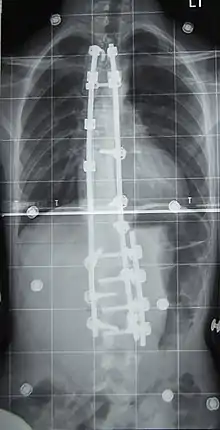

Surgery

Surgery is usually recommended by orthopedists for curves with a high likelihood of progression (i.e., greater than 45 to 50° of magnitude), curves that would be cosmetically unacceptable as an adult, curves in people with spina bifida and cerebral palsy that interfere with sitting and care, and curves that affect physiological functions such as breathing.[98][99]

Surgery is indicated by the Society on Scoliosis Orthopaedic and Rehabilitation Treatment (SOSORT) at 45 to 50°[4] and by the Scoliosis Research Society (SRS) at a Cobb angle of 45°.[100] SOSORT uses the 45 to 50° threshold as a result of the well-documented, plus or minus 5° measurement error that can occur while measuring Cobb angles.[100]

Surgeons who are specialized in spine surgery perform surgery for scoliosis. To completely straighten a scoliotic spine is usually impossible, but for the most part, significant corrections are achieved.[101]

The two main types of surgery are:

- Anterior fusion: This surgical approach is through an incision at the side of the chest wall.

- Posterior fusion: This surgical approach is through an incision on the back and involves the use of metal instrumentation to correct the curve.

One or both of these surgical procedures may be needed. The surgery may be done in one or two stages and, on average, takes four to eight hours.